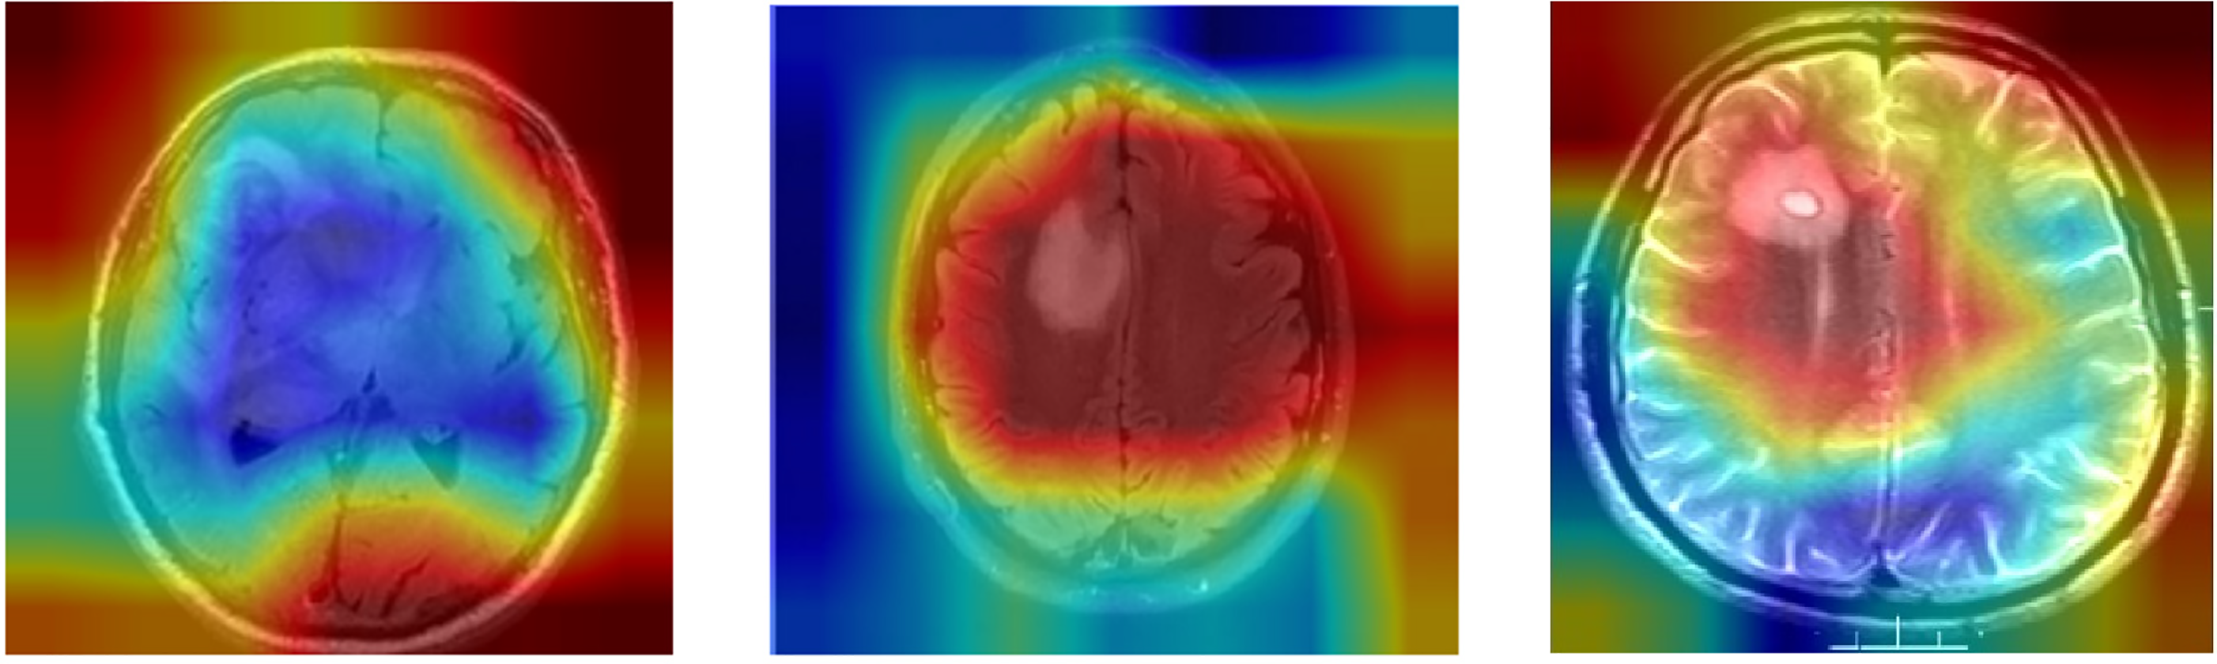

To visually demonstrate how the model processes and interprets MRI images, we present several Grad-CAM heatmaps, as shown in Fig. 6. A heatmap overlay on an MRI image, where the red-to-yellow gradient indicates areas of the highest importance, confirms that the tumor region is correctly identified. Fig. 7 illustrates the heatmaps generated by the basic CNN, the original DenseNet, and our modified DenseNet, highlighting the improved focus and clarity of our model. Fig. 8 shows a more detailed heatmap for MRI images, where tumors are not easily defined or are located in abnormal areas, illustrating how the model performs under stress.

Figure 8: Grad-CAM visualization on edge case scenarios

Fig. 9 illustrates the working of the model to give focus on the tumor region, justifying its diagnostic ability. These Grad-CAM heat map zoning convincingly show that the model draws its predictions from relevant parts of the pattern suitable for diagnosis. It presents a simplified and comprehensible format through which the model’s actions can be easily explained to medical practitioners, thereby motivating clinical integration. Table 7 presents the results of an ablation study analyzing the impact of different architectural modifications on the DenseNet model’s performance.